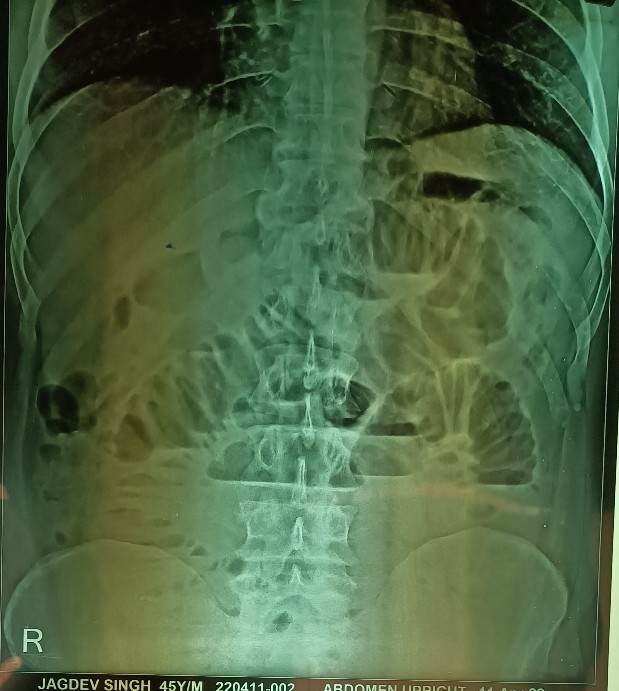

An obstructed paraumbilical hernia (dilated bowel loops with air-fluid levels on X-ray), was explored under spinal anesthesia in a 45 years old male, addicted to opium. The obstructed small bowel loop was found to be strangulated with changes of gangrene in it. The strangulated loop was released, the gangrenous part was resected and an end-to-end anastomosis performed. The hernial defect was then repaired without a prolene mesh.